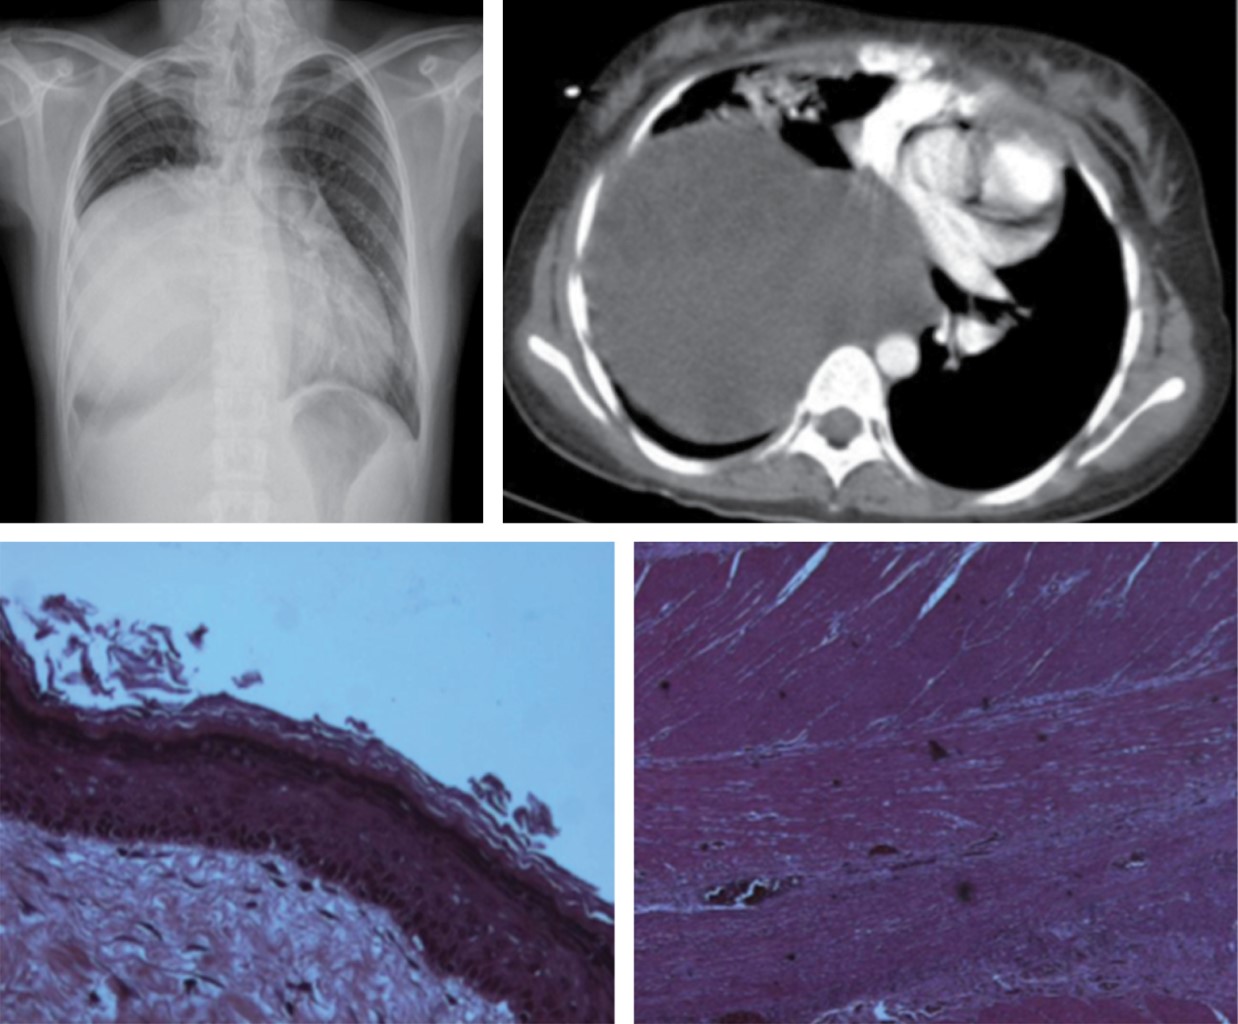

Los hallazgos tomográficos incluyen colecciones líquidas, gas en el mediastino, incremento en la atenuación de la grasa mediastinal, ensanchamiento mediastinal, derrame pleural, derrame pericárdico y presencia de linfadenopatía, en asociación con anormalidades periesternales tales como edema de tejidos blandos, separación esternal con resorción ósea marginal, esclerosis y osteomielitis (Figura 2). Los primeros dos hallazgos son caracterizados en la literatura como altamente positivos.7

Las colecciones mediastinales de 20 UH o menos es indicador de la presencia de contenido líquido; sin embargo, densidades altas sugieren la presencia de sangre que no excluye la presencia de una infección concomitante.

El diagnóstico diferencial de colecciones líquidas loculadas incluyen los seromas posquirúrgicos, los cuales muestran ausencia de realce de su pared con el medio de contraste. Aunque, las colecciones líquidas de mediastinitis pueden no presentar realce si se presentan dentro de la primera semana posoperatoria.

Los hallazgos radiológicos son: ensanchamiento mediastinal generalizado en tomografía con incremento en la atenuación de la grasa mediastinal (similar a la del agua). Una masa focal no es visible. La afectación puede estar asociada con engrosamiento septal interlobular. El engrosamiento pleural o derrame pleural es visto en casi todos los pacientes (Figura 5).